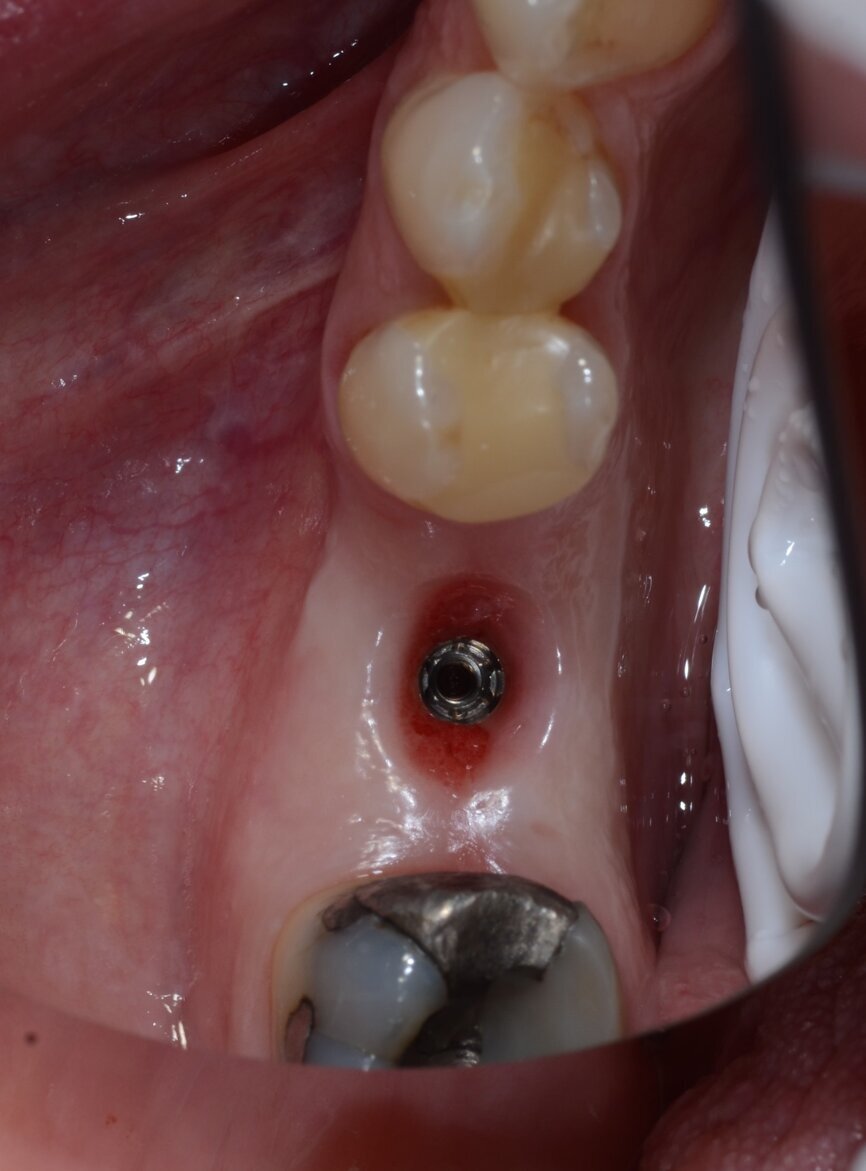

Fig. 15: Extraordinary keratinisation pattern visible when the temporary crown was removed.

Fig. 8: Favourable soft-tissue healing after six weeks.